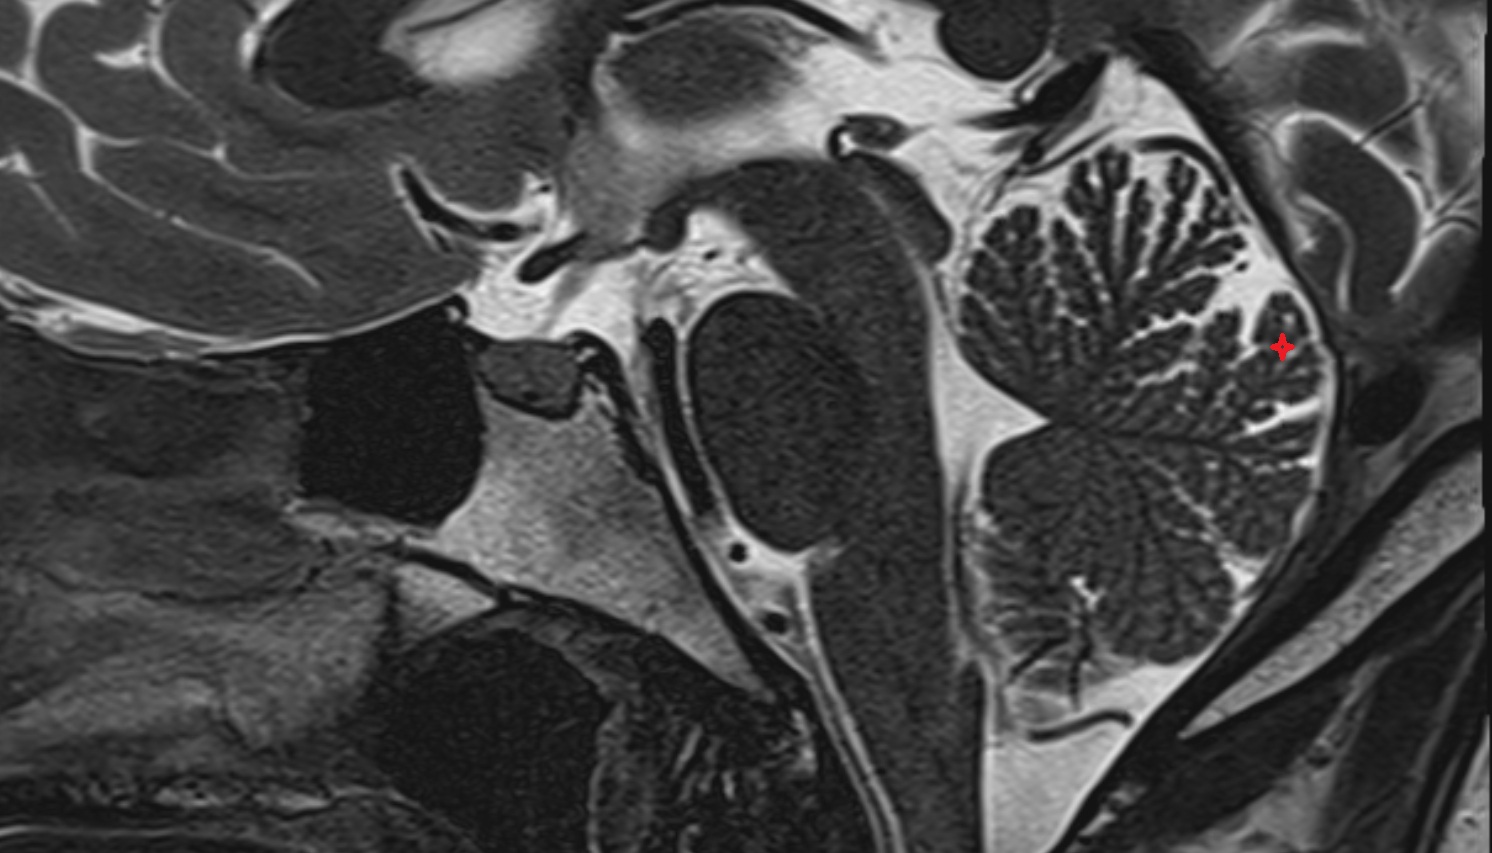

- White matter of cerebellum (Arbor vitae)

- Central lobule (II & III) of Cerebellum

- Culmen (IV, V) of Cerebellum

- Declive (VI) of Cerebellum

- Folium (VII) of Cerebellum

- Tuber of vermis (VII)

- Pyramid of vermis (VIII)

- Uvula of vermis (IX)

- Nodule of vermis (X)

- Cerebellar tonsil (H IX)